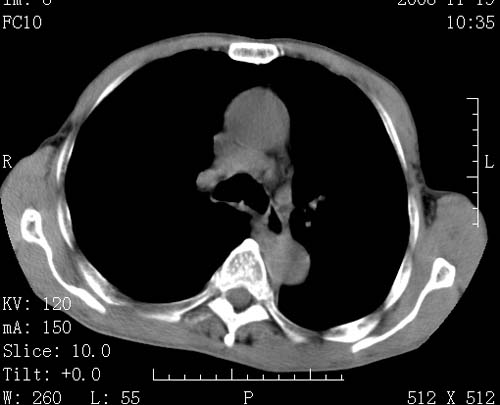

标题: CT16691:m 67 胃镜确诊食管下段及贲门癌 [打印本页]

标题: CT16691:m 67 胃镜确诊食管下段及贲门癌

术前查体,双肺部结节是转移?结核?请点评

1)符合食管癌表现。2)两肺及纵隔淋巴结多发性转移瘤。3)左肺上叶舌段及两肺下叶炎症感染。

食管癌伴双肺转移,评述:肺部毛细血管网丰富,全身血液均快速流经肺部,癌细胞容易过滤定植,形成转移瘤,影象特点为以毛细血管末梢为中心的结节灶,边缘光滑锐利,少见有中心空洞着,不同来源的转移瘤可有各自特点,如甲状腺癌为双肺弥漫性微结节,本例有原发灶,双肺影象灶典型,左肺舌段条带状网格样伴胸膜天幕征,可视为癌性淋巴管炎。

符合食管癌表现。两肺及纵隔淋巴结多发性转移瘤。双肺还有支扩表现.

左肺舌段有斑点钙化灶,能否说明是结核而不是转移?如果是转移将放弃手术改成化疗,如果是结核将考虑择期手术